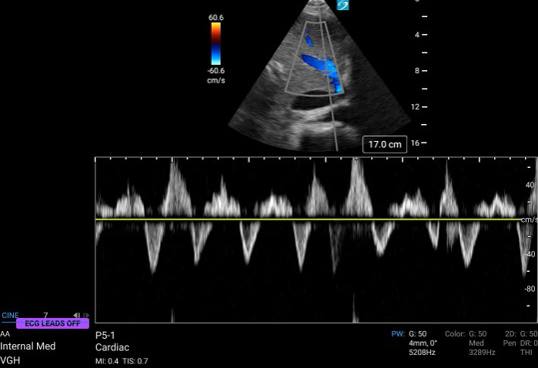

Cardiac ultrasound

A4C